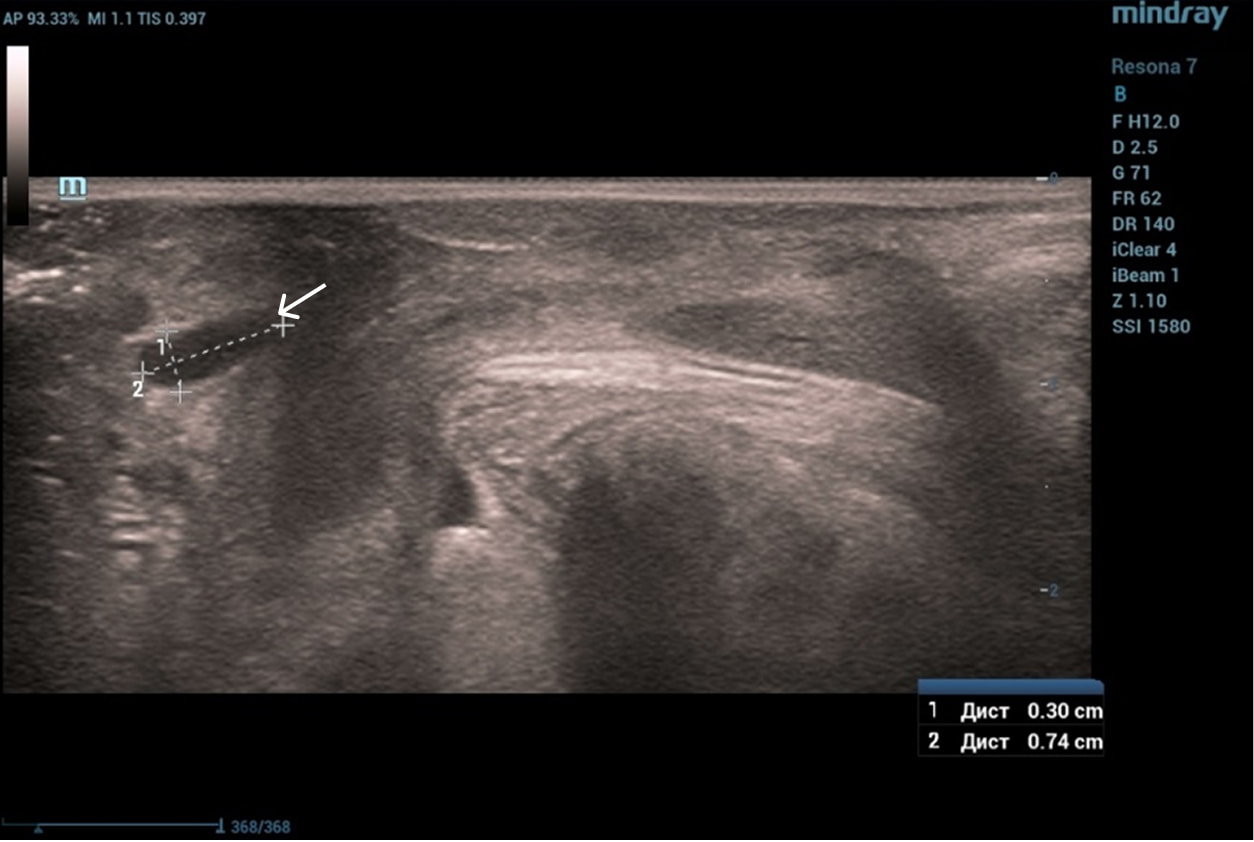

Эхограммы периуретральной области

Трансперинеальный доступ, линейный датчик.

Слева от уретры округлое образование с четкой капсулой и мелкодисперсной взвесью размерами 1,5×1,0 см (филлер с воспалением), справа — анэхогенное овоидное образование (филлер).

Эхограмма 1

Эхограмма 2